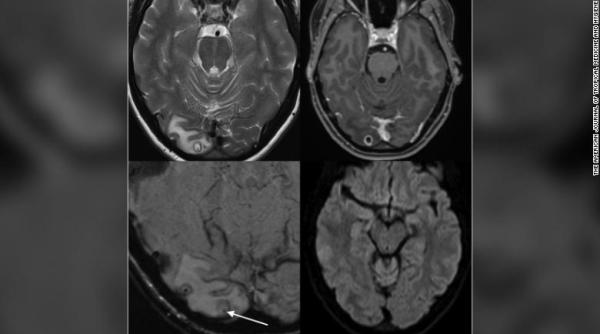

Caz demn de Dr. House: Suferea de migrene groaznice. La RMN s-a văzut că avea VIERMI în CREIER 07 Octombrie 2020